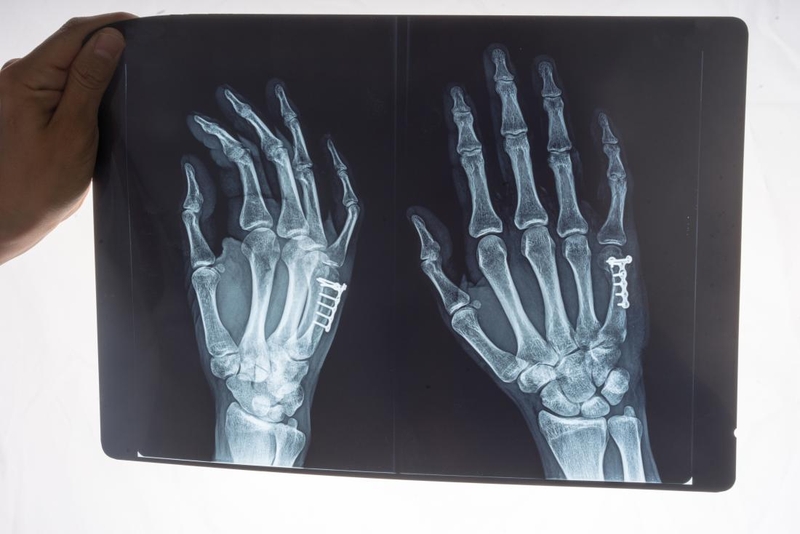

• Chụp X-quang: Thông qua hình ảnh vùng cổ tay được chụp bằng X-quang, bác sĩ có thể hình dung được tình trạng thương tổn của dây chằng ở cổ tay. Sau đó phân loại tình trạng bong gân của bạn đang ở cấp độ nào. Trường hợp nếu là bong gân mãn tính, thì hình ảnh X-quang còn giúp cho bác sĩ điều trị quan sát được xương cổ tay và các chấn thương dây chằng liên quan.

Thời gian điều trị bong gân cổ tay bao lâu thì khỏi 2 Xác định tình trạng bong gân bằng các phương pháp và xét nghiệm như chụp X-quang, siêu âm khớp, chụp cộng hưởng MRI, chụp cắt lớp vi tính nhiều máy dò khớp (MDCT),...